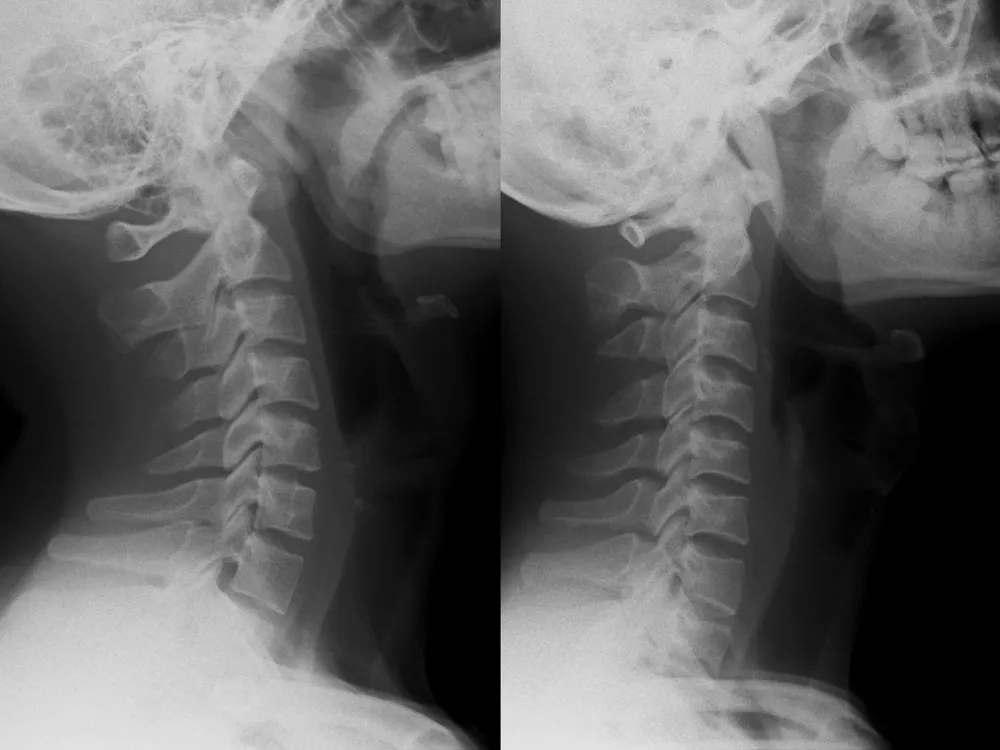

Sau khi thăm khám và chỉ định chụp X-quang cột sống cổ thẳng nghiêng, kết quả cho thấy cột sống cổ bệnh nhân mất hoàn toàn độ cong sinh lý (còn gọi là cổ thẳng), khiến các đốt sống cổ gần như xếp dọc thay vì có độ ưỡn ra trước như bình thường.

Hình ảnh X-quang cột sống cổ bình thường (trái) và mất đường cong sinh lý cột sống cổ (phải). Ảnh: BVCC